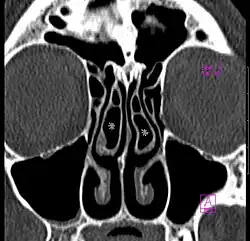

Concha bullosa

A concha bullosa is a pneumatized (air-filled) cavity within a nasal concha, also known as a turbinate.[1] Bullosa refers to the air-filled cavity within the turbinate.[1] It is a normal anatomic variant seen in up to half the population. Occasionally, a large concha bullosa may cause it to bulge sufficiently to obstruct the opening of an adjacent sinus, possibly leading to sleeping apnea or breathing disorder related to areas innervated by the trigeminal nerve.[2] In such a case the turbinate can be reduced in size by endoscopic nasal surgery (turbinectomy). The presence of a concha bullosa is often associated with deviation of the nasal septum toward the opposite side of the nasal cavity.[3]